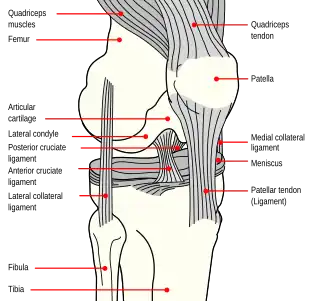

Structure

The knee is a modified hinge joint, a type of synovial joint, which is composed of three functional compartments: the patellofemoral articulation, consisting of the patella, or "kneecap", and the patellar groove on the front of the femur through which it slides; and the medial and lateral tibiofemoral articulations linking the femur, or thigh bone, with the tibia, the main bone of the lower leg.[6] The joint is bathed in synovial fluid which is contained inside the synovial membrane called the joint capsule. The posterolateral corner of the knee is an area that has recently been the subject of renewed scrutiny and research.[7]

Articular bodies

The main articular bodies of the femur are its lateral and medial condyles. These diverge slightly distally and posteriorly, with the lateral condyle being wider in front than at the back while the medial condyle is of more constant width.[10]: 206 The radius of the condyles' curvature in the sagittal plane becomes smaller toward the back. This diminishing radius produces a series of involute midpoints (i.e. located on a spiral). The resulting series of transverse axes permit the sliding and rolling motion in the flexing knee while ensuring the collateral ligaments are sufficiently lax to permit the rotation associated with the curvature of the medial condyle about a vertical axis.[10]: 194–95

The pair of tibial condyles are separated by the intercondylar eminence[10]: 206 composed of a lateral and a medial tubercle.[10]: 202

The patella also serves an articular body, and its posterior surface is referred to as the trochlea of the knee.[11] It is inserted into the thin anterior wall of the joint capsule.[10]: 206 On its posterior surface is a lateral and a medial articular surface,[10]: 194 both of which communicate with the patellar surface which unites the two femoral condyles on the anterior side of the bone's distal end.[10]: 192

Ligaments

The ligaments surrounding the knee joint offer stability by limiting movements and, together with the menisci and several bursae, protect the articular capsule.[19]

Intracapsular

The knee is stabilized by a pair of cruciate ligaments. These ligaments are both extrasynovial, intracapsular ligaments.[20] The anterior cruciate ligament (ACL) stretches from the lateral condyle of femur to the anterior intercondylar area.[13] The ACL prevents the tibia from being pushed too far anterior relative to the femur.[13] It is often torn during twisting or bending of the knee.[21] The posterior cruciate ligament (PCL) stretches from medial condyle of femur to the posterior intercondylar area. This ligament prevents posterior displacement of the tibia relative to the femur.[13] Injury to this ligament is uncommon but can occur as a direct result of forced trauma to the ligament.

The transverse ligament stretches from the lateral meniscus to the medial meniscus. It passes in front of the menisci. It is divided into several strips in 10% of cases.[10]: 208 The two menisci are attached to each other anteriorly by the ligament.[22] The posterior (of Wrisberg) and anterior meniscofemoral ligaments (of Humphrey) stretch from the posterior horn of the lateral meniscus to the medial femoral condyle. They pass anterior and posterior to the posterior cruciate ligament respectively.[13][10]: 208 The meniscotibial ligaments (or "coronary") stretches from inferior edges of the menisci to the periphery of the tibial plateaus.

Extracapsular

The patellar ligament connects the patella to the tuberosity of the tibia. It is also occasionally called the patellar tendon because there is no definite separation between the quadriceps tendon (which surrounds the patella) and the area connecting the patella to the tibia.[23] This very strong ligament helps give the patella its mechanical leverage[24] and also functions as a cap for the condyles of the femur. Laterally and medially to the patellar ligament, the lateral and medial retinacula connect fibers from the vasti lateralis and medialis muscles to the tibia. Some fibers from the iliotibial tract radiate into the lateral retinaculum and the medial retinaculum receives some transverse fibers arising on the medial femoral epicondyle.[10]: 206

The medial collateral ligament (MCL a.k.a. "tibial") stretches from the medial epicondyle of the femur to the medial tibial condyle. It is composed of three groups of fibers, one stretching between the two bones, and two fused with the medial meniscus. The MCL is partly covered by the pes anserinus and the tendon of the semimembranosus passes under it.[10]: 206 It protects the medial side of the knee from being bent open by a stress applied to the lateral side of the knee (a valgus force).[10]: 206

The lateral collateral ligament (LCL a.k.a. "fibular") stretches from the lateral epicondyle of the femur to the head of fibula. It is separate from both the joint capsule and the lateral meniscus.[10]: 206 It protects the lateral side from an inside bending force (a varus force). The anterolateral ligament (ALL) is situated in front of the LCL.